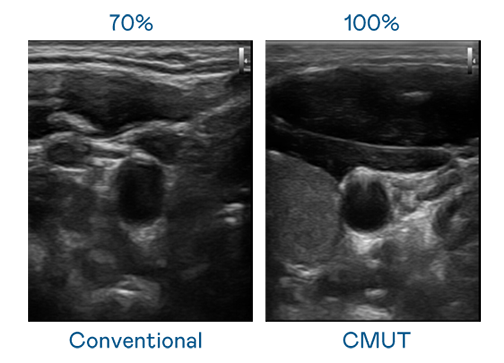

CMUT 技術是一種用電容式微機電元件來產生超音波訊號的技術。與傳統 PZT 壓電式技術相比,CMUT 頻寬增加 30%,更寬頻的超音波訊號讓影像解析度大幅提升,是實現高影像品質醫療超音波掃描、促進精準醫療發展的關鍵技術。

超音波影像的解析度高低,首先取決於探頭能發出的訊號頻寬。南宫ng CMUT 可提供高清晰的超音波訊號,提供高頻寬、高靈敏度、影像紋理細節更高的超音波影像,協助醫護人員縮短影像判讀時間及利用精準的醫療影像進行診斷。